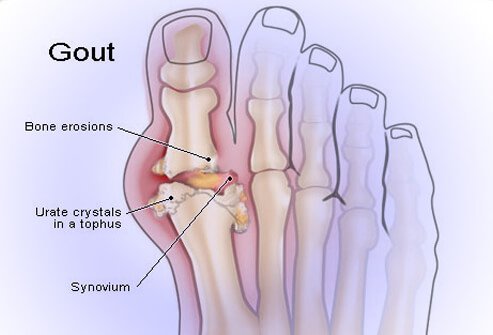

Gout is a form of acute arthritis that causes severe pain and swelling in the joints. It most commonly affects the big toe, but may also affect the heel, ankle, hand, wrist, or elbow. It affects the spine often enough to be a factor in back pain. Gout usually comes on suddenly, goes away after 5-10 days, and can keep recurring. Gout is different from other forms of arthritis because it occurs when there are high levels of uric acid circulating in the blood, which can cause urate crystals to settle in the tissues of the joints.